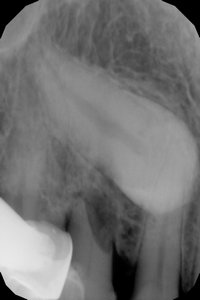

Дочке 5 лет. Выпали два нижних передних зуба, третий шатается, рядом с ним прорезался постоянный зуб, но растет он неровно (мешает шатающийся зуб).

Скажите, пожалуйста, может ли он со временем выровняется, или уже ничего не сделать? Может пойти к врачу, поставить брекеты?

Необходимо обратитьсямк ортодонту. В этом возрасте брекеты не ставятся, возможно, необходимо будет установить пластинки. Сам зуб, конечно, на место не встанет, необходимо стимулировать его правильное прорезание.